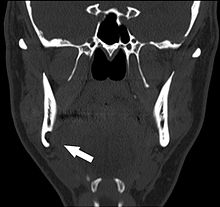

Coronal computed tomograph of the same person (Stafne defect arrowed).

Stafne's defect is usually discovered by chance during routine dental radiography.[4] Radiographically, it is a well-circumscribed, monolocular, round, radiolucent defect, 1–3 cm in size, usually between the inferior alveolar nerve (IAN) and the inferior border of the posterior mandible between the molars and the angle of the jaw. It is one of the few radiolucent lesions that can occur below the IAN. The border is well corticated and it will have no effect on the surrounding structures. Computed tomography (CT) will show a shallow defect through the medial cortex of the mandible with a corticated rim and no soft tissue abnormalities, with the exception of a portion of the submandibular gland. Neoplasms, such as metastatic squamous cell carcinoma to the submandibular lymph nodes or a salivary gland tumour, could create a similar appearance but rarely have such well defined borders and can usually be palpated in the floor of the mouth or submandibular triangle of the neck as a hard mass. CT and clinical exam is typically sufficient to distinguish between this and a Stafne defect. The Stafne defect also tends to not increase in size or change in radiographic appearance over time (hence the term "static bone cyst"), and this can be used to help confirm the diagnosis.[4] Tissue biopsy is not usually indicated, but if carried out, the histopathologic appearance is usually normal salivary gland tissue. Sometimes attempted biopsy of Stafne defects reveals an empty cavity (possibly because the gland was displaced at the time of biopsy), or other contents such as blood vessels, fat, lymphoid or connective tissues. Defects of the anterior lingual mandible may require biopsy for correct diagnosis at this unusual location.[2] The radiolucent defect here may be superimposed on the lower anterior teeth and be mistaken for an odontogenic lesion. Sometimes the defect may interrupt the contour of the lower border of the mandible, and may be palpable. Sialography may be sometimes used to help demonstrate the salivary gland tissue within the bone.